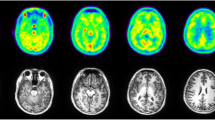

At baseline, [18F]SF51 readily entered monkey brain; its uptake peaked at five to 15 min post-injection (mean SUV peak 2.0 ± 0.1) and was followed by moderate wash-out (Fig. 2B). Brain activity decreased to 50% of the peak by 110 min and to 30% of the peak by 180 min. The mean SUV peak after pre-blockade with 5 mg/kg PK11195 was higher (3.0 ± 0.5), and the wash-out phase was faster, likely because of reduced retention of the radioligand (Fig. 2B). As expected from the known distribution of TSPO in human and monkey brain [6], the activity was widespread and fairly uniform in the cortical gray matter, cerebellum, and thalamus (Fig. 3). At baseline, a low uptake in the skull was observed (Supplementary Fig. S3) that did not generate significant spill-over at visual analysis. This uptake was blocked by both PK11195 and PBR28 and is therefore likely due to extracerebral specific binding, not to deposition of 18F-fluoride ion into bone after defluorination.

Parametric images of total 18 kDa translocator protein (TSPO) binding (VT/fP) for [18F]SF51 in monkey brain at baseline (top row) and after PK11195 pre-blockade (5 mg/kg, middle row). The template MRI of monkey brain is shown in the bottom row. Each total distribution volume corrected for free parent fraction in plasma (VT/fP) image was generated by Logan Plot using 0–180 min of PET data graphical analysis